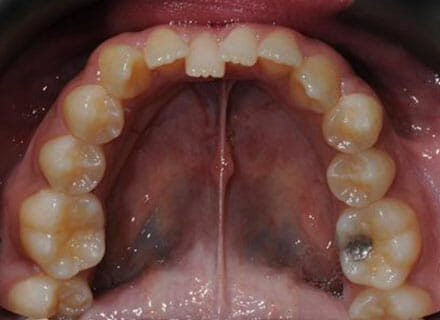

This patient came to us because she hated her smile: it was too narrow, the upper front teeth were all crowded into each other and twisted. She couldn’t eat a sandwich properly with the front teeth because of the gap – the open bite. We were able to expand both jaws to make space to align all the teeth without having to extract – in about 18 months using clear brackets.